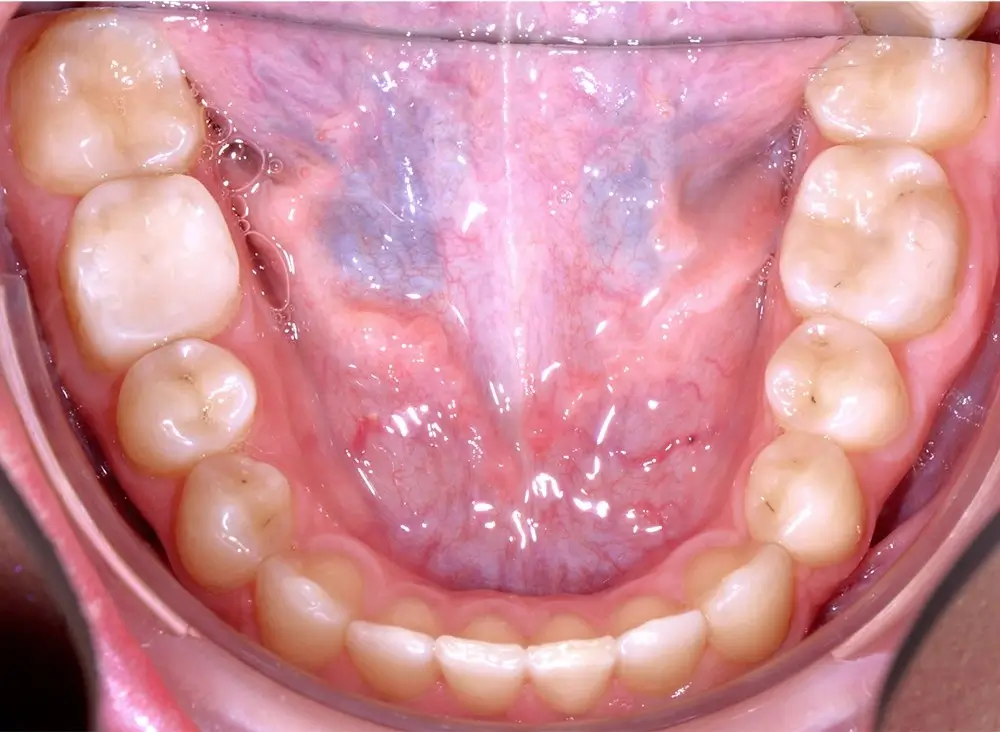

Кейс 8

Количество кап ВЧ 24

Количество кап НЧ 24

ДО